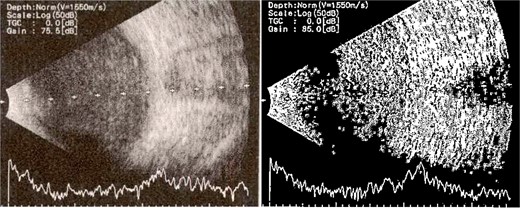

Patient 1: A 66-year-old Sudanese male presented to the emergency room with severe pain in his right eye 2 days post-phacoemulsification. Examination revealed only light perception, elevated intraocular pressure (IOP), a hazy cornea, hypopyon, and extensive pupillary membrane (Fig. 1). A B-scan ultrasound (Fig. 2). He underwent a vitreous tap and received intravitreal antibiotics.

B-scan ultrasound demonstrating mild to moderate vitritis in endophthalmitis case in patient 1.